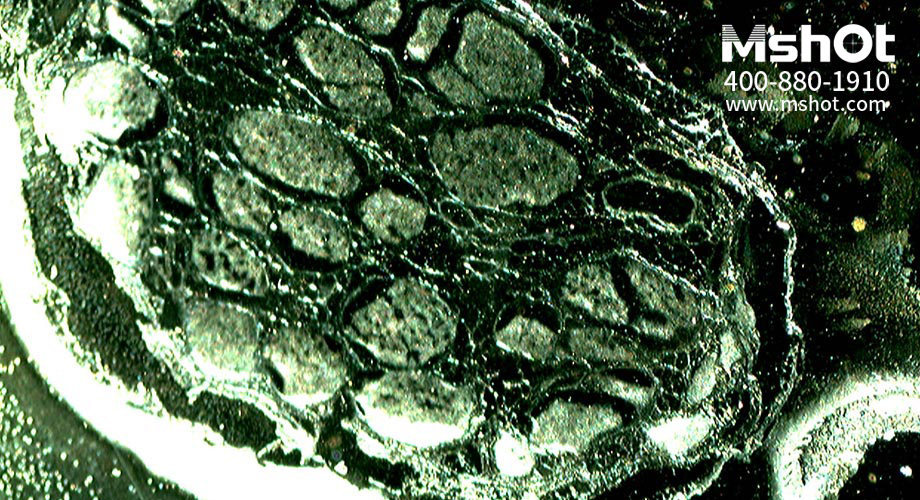

神經(jīng)纖維切片顯微圖片。 (操作提示:點(diǎn)擊圖片或使用鍵盤上的方向鍵來轉(zhuǎn)換要查看的圖片)